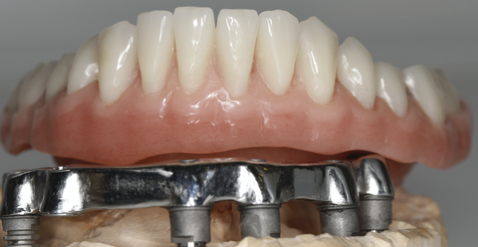

Mai întâi se realizează bara (Fig. 3.9.10) peste care se va aplica viitoarea lucrare. Apoi se realizează o machetă a lucrării pentru a analiza corectitudinea ocluziei (mușcăturii) (Fig. 3.9.11) precum și înălțimea dinților și aspectul facial al pacientului (Fig. 3.9.12, și Fig. 3.9.13).

Proteza stă pe bară fără să se miște deoarece în baza protezei există elemente de ancorare siliconate de culoare galbenă așezate aproape una de cealaltă pe toată suprafața bazei (Fig. 3.9.14). Acele elemente creează fricțiune între proteză și bară și nu permite desprinderea involuntară a acesteia, chiar dacă pacientul mestecă alimente lipicioase. Proteza poate fi îndepărtată cu mâna doar printr-o acțiune voluntară a pacientului. Acest tip de lucrare reface funcția masticatorie, pacienții bucurându-se de toate tipurile de alimente fără grija că proteza va cădea sau va sări.

Aspectul lucrării este unul natural, aceasta îmbunătățind estetica generală și fizionomia pacientului prin redarea conturului feței și plenitudinii obrajilor și a buzelor. Refacerea funcției masticatorii și redarea fizionomiei va aduce o îmbunătățire semnificativă a calității vieții pacienților care aleg acest tip de tratament (Fig. 3.9.15).